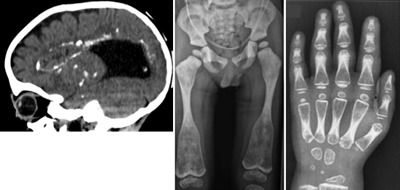

これらの研究のなかで、最近収集した難病患者の中に、共通の骨格、脳神経系の異常を持つ3家系7人の患者を発見。骨格には、全身の骨硬化、脊椎の形成異常、長管骨と短管骨の骨幹端部の拡大などの特徴的な異常が、脳には、脳室周囲の石灰化を伴う白質脳症様の神経変性とダンディ・ウォーカー奇形などの脳奇形が認められた。このような骨格、脳神経系の異常の組み合わせは過去に報告がなく、新たな症候群であると考えられ、今回、その原因遺伝子の同定を試みた。

今回、血球系の細胞の受容体として知られていたCSF1Rの機能喪失が、広範かつ多様な骨格、脳神経系の異常を持つ、新たなタイプの難病の原因となることが明らかになった。骨格の異常は、これまでに知られていた骨・関節の遺伝病の異骨硬化症、もしくはPyle病(骨幹端異形成症)に類似している。脳の異常はHDLSと同様だが、より早期に発症し、重篤で、かつHDLSでは見られない、先天的な奇形を伴っていた。